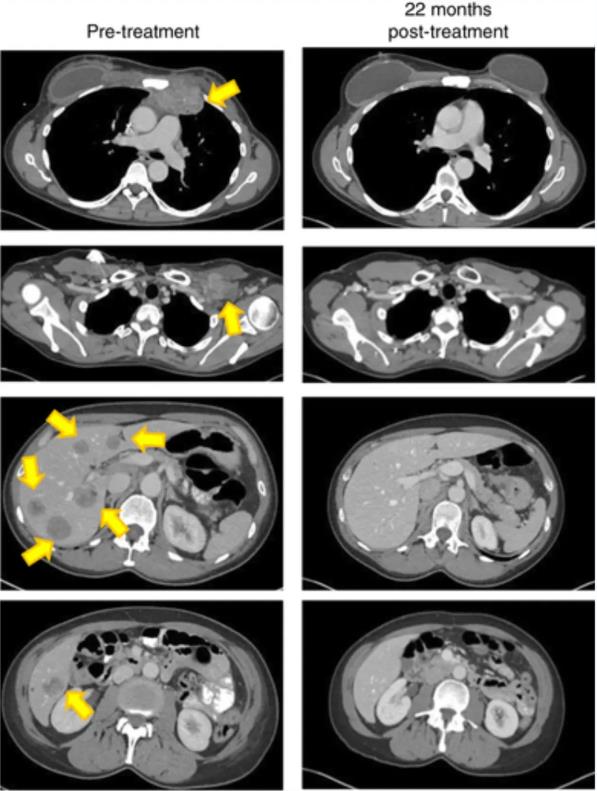

虽然治疗过程是漫长且艰辛的,但幸运的是,在治疗5个月后(2016年5月),复查影像学显示,她的病灶竟奇迹般的“消失”了(详见下图),肿瘤缩小到足以停止服用止痛药,而且生活也重回正轨。截至数据统计止,Judy已存活超过3年!她甚至在2018年3月,完成了1,200英里环绕佛罗里达州的皮划艇之旅,并开始期待未来几十年的生活!可以说TIL疗法,奇迹般地将Judy从死亡边缘拉了回来。

▼TIL细胞治疗前、治疗后22个月的影像学对比

▲图源“Nat Med”,版权归原作者所有,如无意中侵犯了知识产权,请联系我们删除